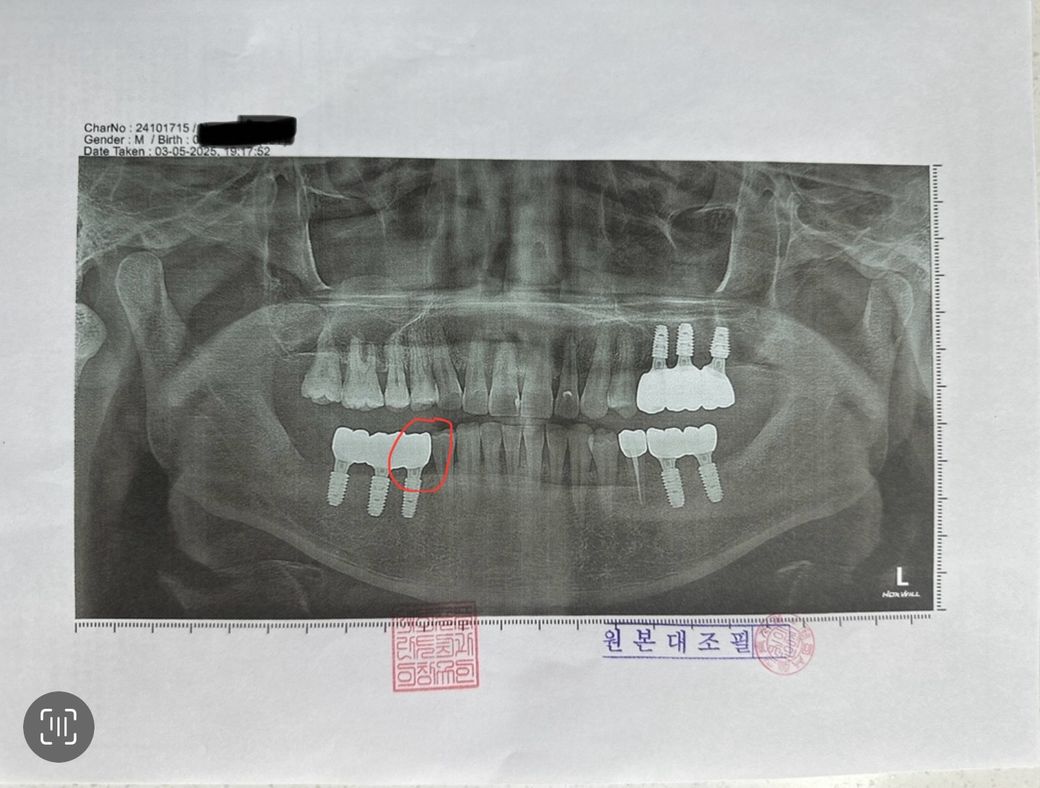

워터픽만 하면 좀 통증이 있는데 잘못된건가요? 젤 수압 쌘걸로 하긴 하는데 묶여있는 임플란트 인데 한개만 통증이 있어서요..

치과를 가서 문의를 해야하는지...사진에 빨간색 쪽만 통증이 있어요.

• 1번 째 사진

사진상으론 임플란트 식립상태, 뼈상태는 양호해보입니다

다만 임플란트 주위 잇몸에 염증이 있으면 워터픽 사용 시 통증이 있을 수 있으니 치과가서 검사받아보시기 바랍니다